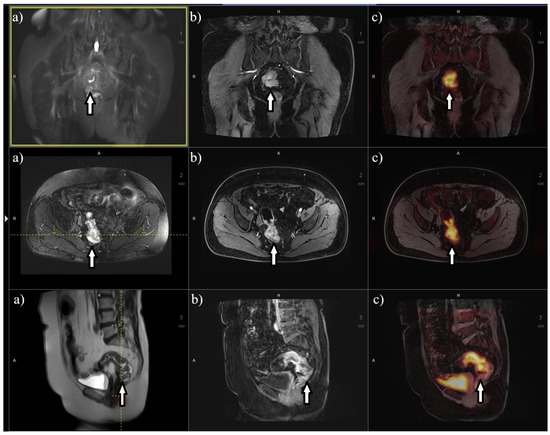

Enhancing Lymphoma Diagnosis, Treatment, and Follow-Up Using 18F-FDG PET/CT Imaging: Contribution of Artificial Intelligence and Radiomics Analysis

Cancers 2024, 16(20), 3511; https://doi.org/10.3390/cancers16203511 - 17 Oct 2024

Lymphoma, encompassing a wide spectrum of immune system malignancies, presents significant complexities in its early detection, management, and prognosis assessment since it can mimic post-infectious/inflammatory diseases. The heterogeneous nature of lymphoma makes it challenging to definitively pinpoint valuable biomarkers for predicting tumor biology [...] Read more.

Lymphoma, encompassing a wide spectrum of immune system malignancies, presents significant complexities in its early detection, management, and prognosis assessment since it can mimic post-infectious/inflammatory diseases. The heterogeneous nature of lymphoma makes it challenging to definitively pinpoint valuable biomarkers for predicting tumor biology and selecting the most effective treatment strategies. Although molecular imaging modalities, such as positron emission tomography/computed tomography (PET/CT), specifically 18F-FDG PET/CT, hold significant importance in the diagnosis of lymphoma, prognostication, and assessment of treatment response, they still face significant challenges. Over the past few years, radiomics and artificial intelligence (AI) have surfaced as valuable tools for detecting subtle features within medical images that may not be easily discerned by visual assessment. The rapid expansion of AI and its application in medicine/radiomics is opening up new opportunities in the nuclear medicine field. Radiomics and AI capabilities seem to hold promise across various clinical scenarios related to lymphoma. Nevertheless, the need for more extensive prospective trials is evident to substantiate their reliability and standardize their applications. This review aims to provide a comprehensive perspective on the current literature regarding the application of AI and radiomics applied/extracted on/from 18F-FDG PET/CT in the management of lymphoma patients. Full article